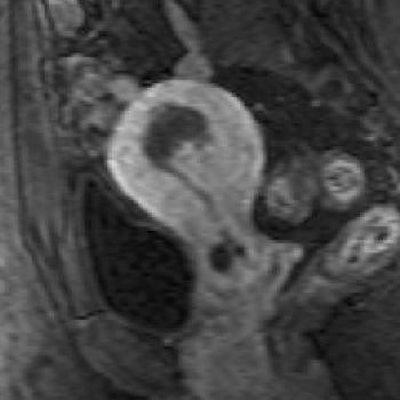

| A 44-year-old woman with asymmetric diffuse adenomyosis. T2-weighted axial image obtained before UAE showed asymmetric diffuse thickening of junctional zone with multiple high-signal-intensity foci within that zone, which is compatible with adenomyosis. |